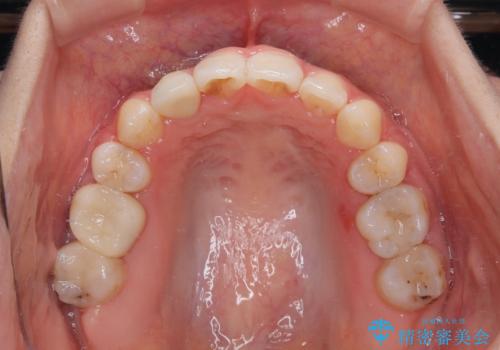

- 前歯のデコボコと口元の突出感を気にして来院された患者様です。

口元の突出感が認められ、更には左右で異なる咬合状態であったため、下顎右側は第二小臼歯を、左側は第一小臼歯を抜去することでバランスを取るような治療計画としました。

また上顎前歯は大臼歯に補綴治療が必要であったため、矯正治療後にオールセラミッククラウンによる補綴治療を行うこととしました。

下顎の抜歯位置を左右で変えることで、最終的に上下正中をほぼ一致させることができました。